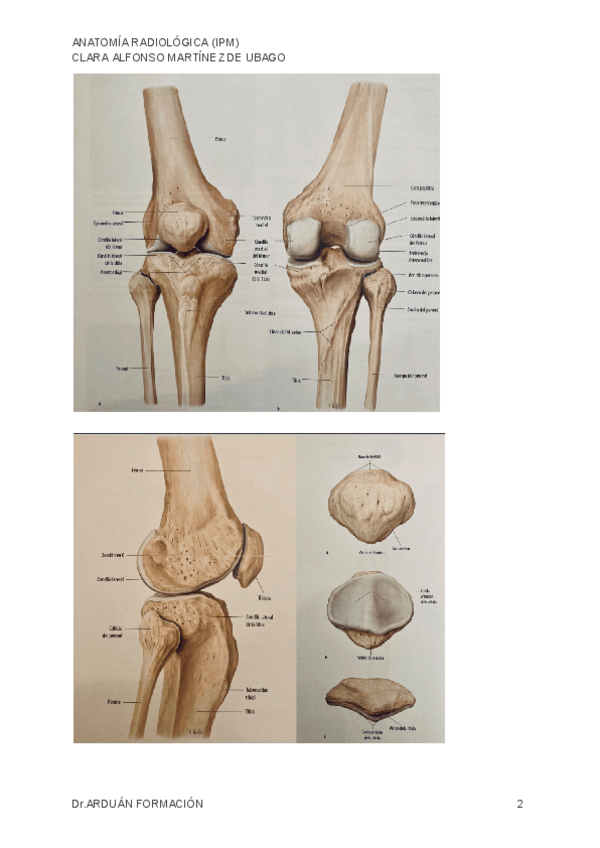

1º Imagen para el diagnóstico y medicina nuclear. Apuntes anatomía. LA RODILLA

4 páginas